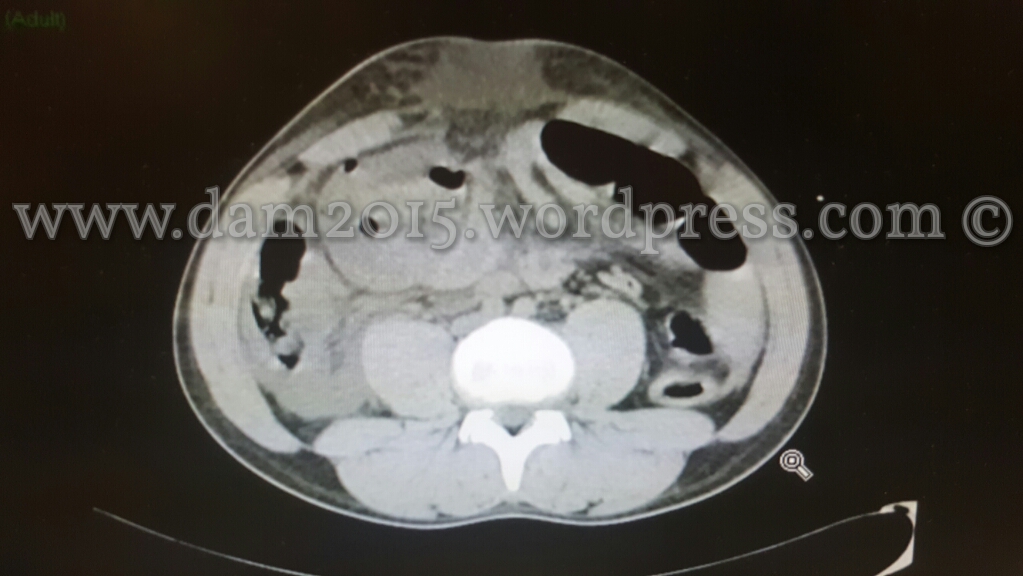

Peggioramento del quadro clinico addominale.

Eseguita nuova TC addome che mostrava incremento dell’imbibizione edematosa-emorragica del tessuto adiposo sottocutaneo e comparsa di marcato ispessimento edematoso delle anse del piccolo intestino ove sembrava apprezzarsi discontinuità della parete intestinale; presenza di bolle di aria libera come per perforazione di viscere cavo.